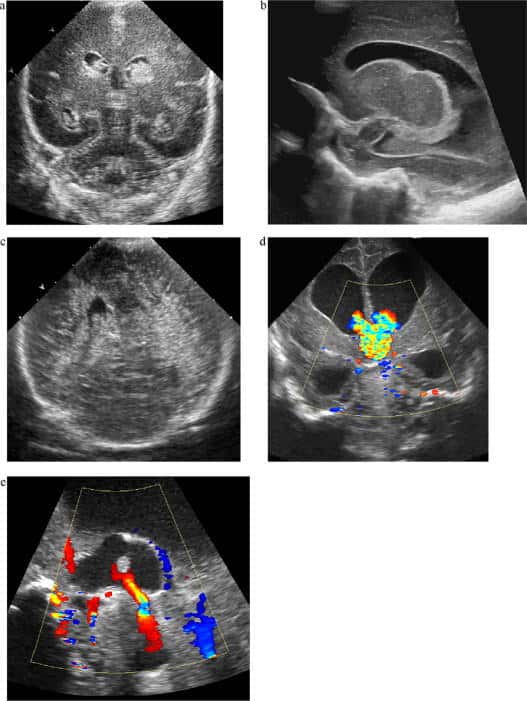

Malformações congênitas

Atualmente, a maioria das malformações cerebrais congênitas é identificada ainda no período fetal. Dessa forma, utiliza-se a ultrassonografia pós-natal principalmente para confirmação diagnóstica e acompanhamento.

Diversas condições podem ser visualizadas de forma satisfatória por neurossonografia, incluindo:

- Diferentes tipos de hidrocefalia.

- Holoprosencefalia.

- Esquizencefalia (especialmente de lábio aberto).

- Malformações septais ou calosas, assim como os tipos malformações de Chiari e Dandy-Walker.

Hidrocefalia

A hidrocefalia pode ser congênita ou adquirida, geralmente secundária a hemorragias, infecções ou lesões ocupando espaço, que comprometem a drenagem do LCR, além de alterações na produção ou reabsorção do líquido.

Nesse contexto, a ultrassonografia neonatal é útil não apenas para identificar a condição e avaliar a anatomia ventricular, mas também para graduar a hidrocefalia, distinguir casos com ou sem hipertensão intracraniana e monitorar a evolução ou resposta ao tratamento. Além disso, medições reprodutíveis do tamanho ventricular permitem comparações com valores normais para a idade, enquanto o prognóstico está mais relacionado à proporção entre parênquima e ventrículos.

O Doppler complementa a avaliação, permitindo estimar a pressão intracraniana e perfusão cerebral, detectando alterações como fluxo diastólico prejudicado em casos de hipertensão.